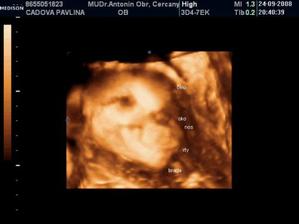

• 24.9.2008 – 4D ultrazvuk, potvrzena holčička